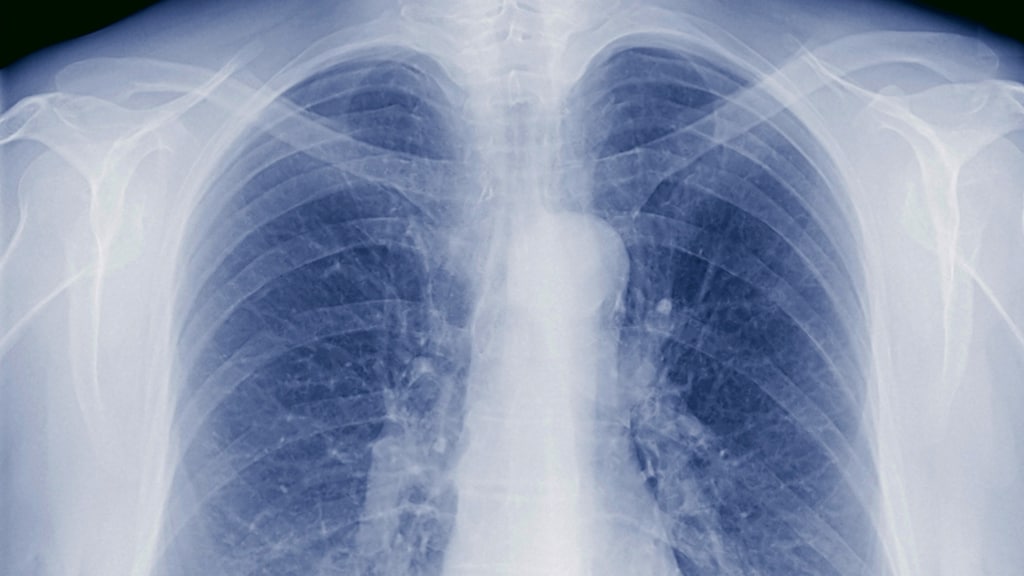

De 51-jarige Rob Stuivenberg, vader van twee kinderen, werd in 2011 voor het eerst ziek. De artsen kwamen er per toeval achter, toen hij een longfoto moest laten maken voor een andere aandoening. 'Tuberculose', was de diagnose van de arts na ziekenhuisonderzoek – 'tering' in de volksmond. 'Je gaat er niet dood aan', hadden ze meteen gezegd. Dus Rob kreeg medicatie en sprak toen over 'een storm in een glas water'.

"Een besmetting zit in een klein hoekje", vervolgt ze. Tbc kan worden overgedragen via de lucht, dus als mensen praten, hoesten, zingen. Patiënten wordt aangeraden dat áls ze moesten hoesten, dit dan in hun hand of elleboog doen.